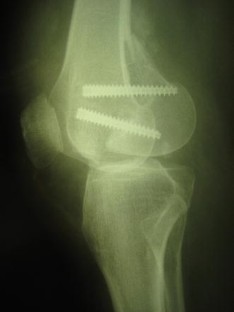

Fig. 3